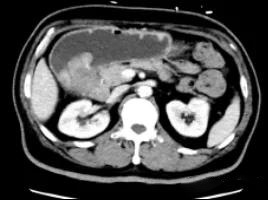

通过放射影像等工具对每个胃癌患者进行精准的术前分期,对于不可切除的局部晚期胃癌患者由肿瘤内科先根据基因检测结果制定个体化的化疗方案,并进行三到四个周期的术前化疗,我们称之为“转化治疗”。

我们之前给一些这样的患者做了三个疗程的化疗之后,肿块奇迹般地缩小了,原来和周围浸润粘连的地方都退缩了,复查CT发现,原来肿瘤周围分界不清的地方都变得清晰了,

转化治疗前

转化治疗后